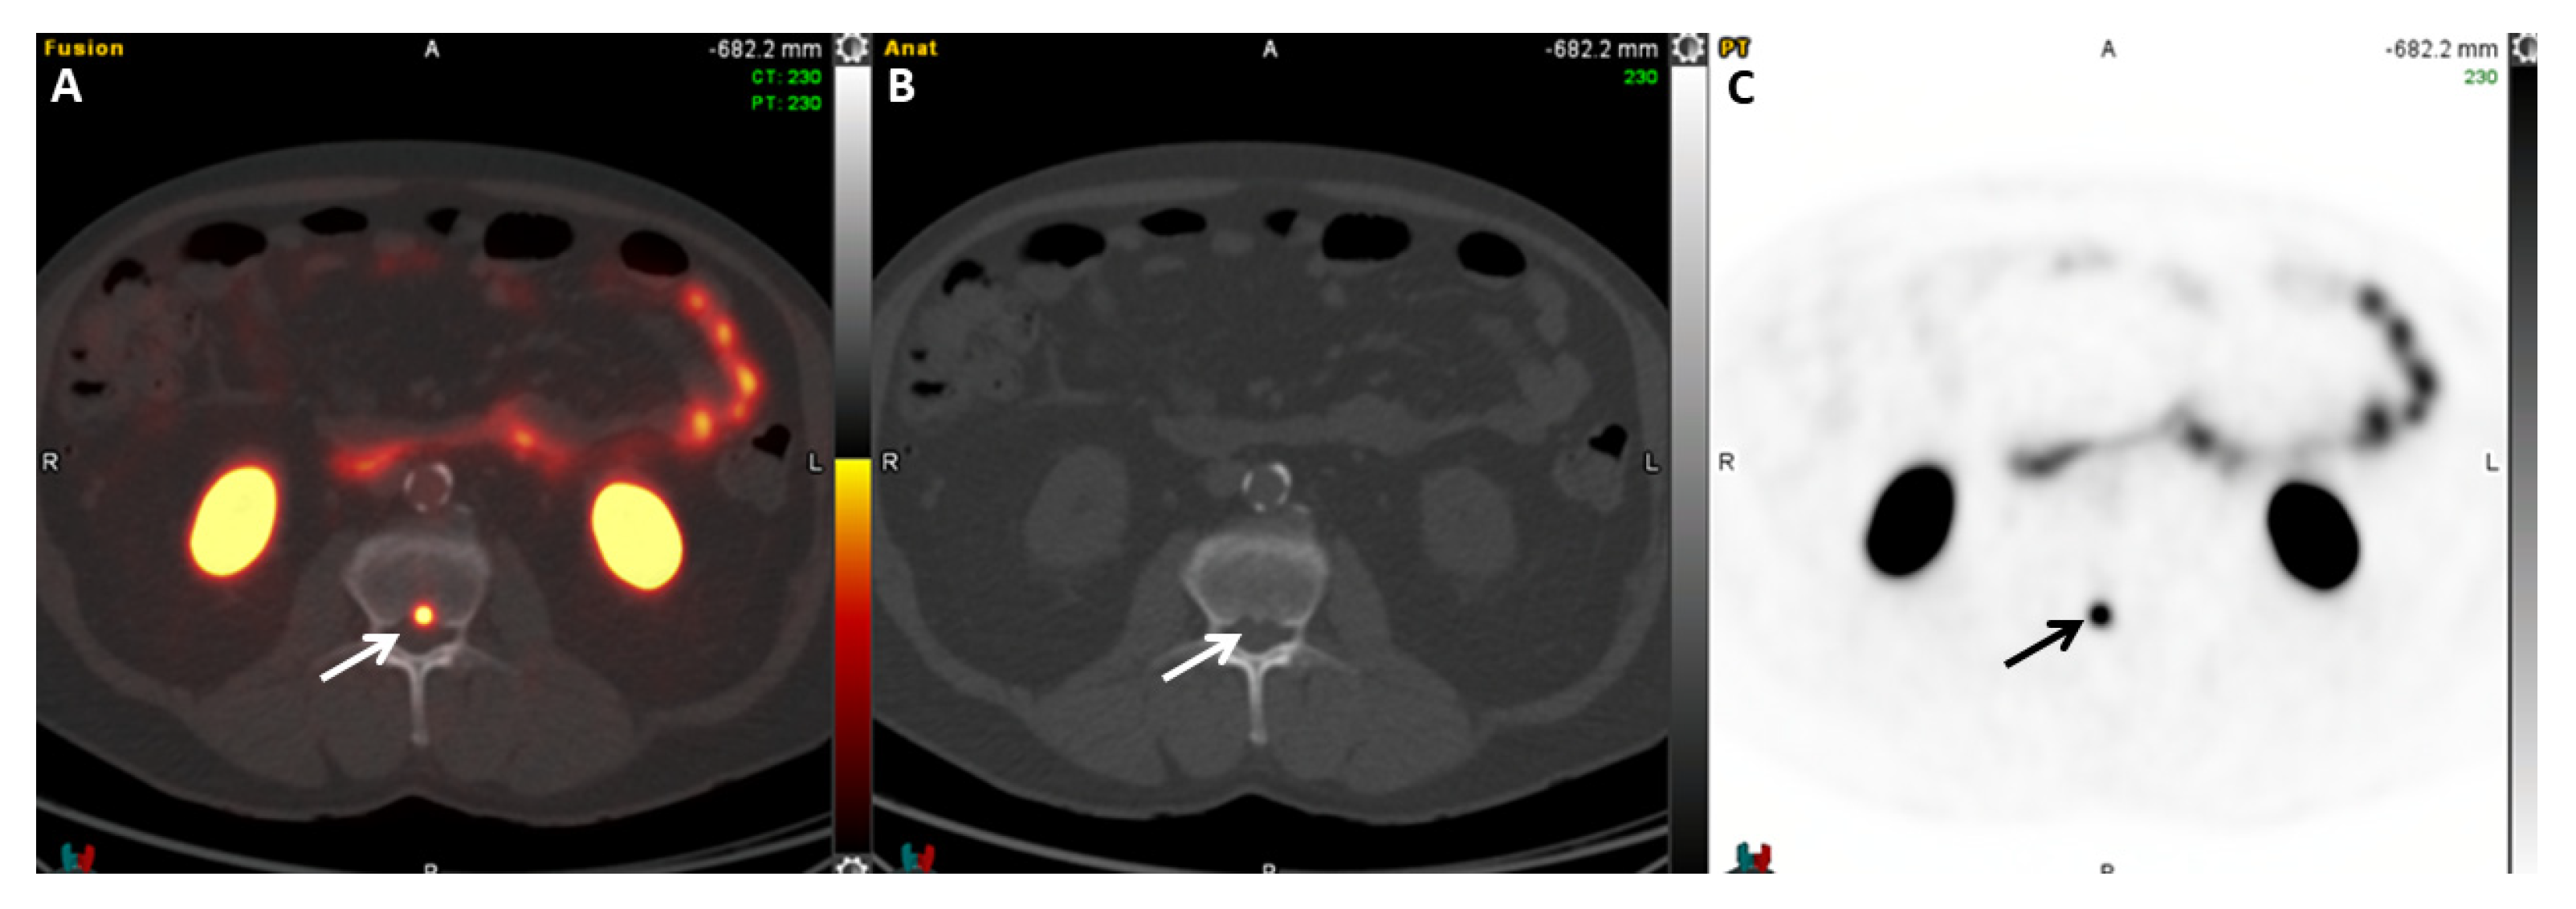

2.5.1. 68Ga-PSMA-11

- Rauscher, I.; Maurer, T.; Fendler, W.P.; Sommer, W.H.; Schwaiger, M.; Eiber, M. 68Ga-PSMA ligand PET/CT in patients with prostate cancer: How we review and report. Cancer Imaging 2016, 16, 14. [Google Scholar] [CrossRef]

- Hofman, M.S.; Hicks, R.J.; Maurer, T.; Eiber, M. Prostate-specific Membrane Antigen PET: Clinical Utility in Prostate Cancer, Normal Patterns, Pearls, and Pitfalls. Radiographics 2018, 38, 200–217. [Google Scholar] [CrossRef]

- Sachpekidis, C.; Afshar-Oromieh, A.; Kopka, K.; Strauss, D.S.; Pan, L.; Haberkorn, U.; Dimitrakopoulou-Strauss, A. 18F-PSMA-1007 multiparametric, dynamic PET/CT in biochemical relapse and progression of prostate cancer. Eur. J. Nucl. Med. Mol. Imaging 2020, 47, 592–602. [Google Scholar] [CrossRef]

- Pattison, D.A.; Debowski, M.; Gulhane, B.; Arnfield, E.G.; Pelecanos, A.M.; Garcia, P.L.; Latter, M.J.; Lin, C.Y.; Roberts, M.J.; Ramsay, S.C.; et al. Prospective intra-individual blinded comparison of [18F]PSMA-1007 and [68 Ga]Ga-PSMA-11 PET/CT imaging in patients with confirmed prostate cancer. Eur. J. Nucl. Med. Mol. Imaging 2022, 49, 763–776. [Google Scholar] [CrossRef]

- Rauscher, I.; Kronke, M.; Konig, M.; Gafita, A.; Maurer, T.; Horn, T.; Schiller, K.; Weber, W.; Eiber, M. Matched-Pair Comparison of 68Ga-PSMA-11 PET/CT and 18F-PSMA-1007 PET/CT: Frequency of Pitfalls and Detection Efficacy in Biochemical Recurrence After Radical Prostatectomy. J. Nucl. Med. Off. Publ. Soc. Nucl. Med. 2020, 61, 51–57. [Google Scholar]

- Seifert, R.; Telli, T.; Opitz, M.; Barbato, F.; Berliner, C.; Nader, M.; Umutlu, L.; Stuschke, M.; Hadaschik, B.; Herrmann, K.; et al. Unspecific 18F-PSMA-1007 Bone Uptake Evaluated Through PSMA-11 PET, Bone Scanning, and MRI Triple Validation in Patients with Biochemical Recurrence of Prostate Cancer. J. Nucl. Med. Off. Publ. Soc. Nucl. Med. 2023, 64, 738–743. [Google Scholar]